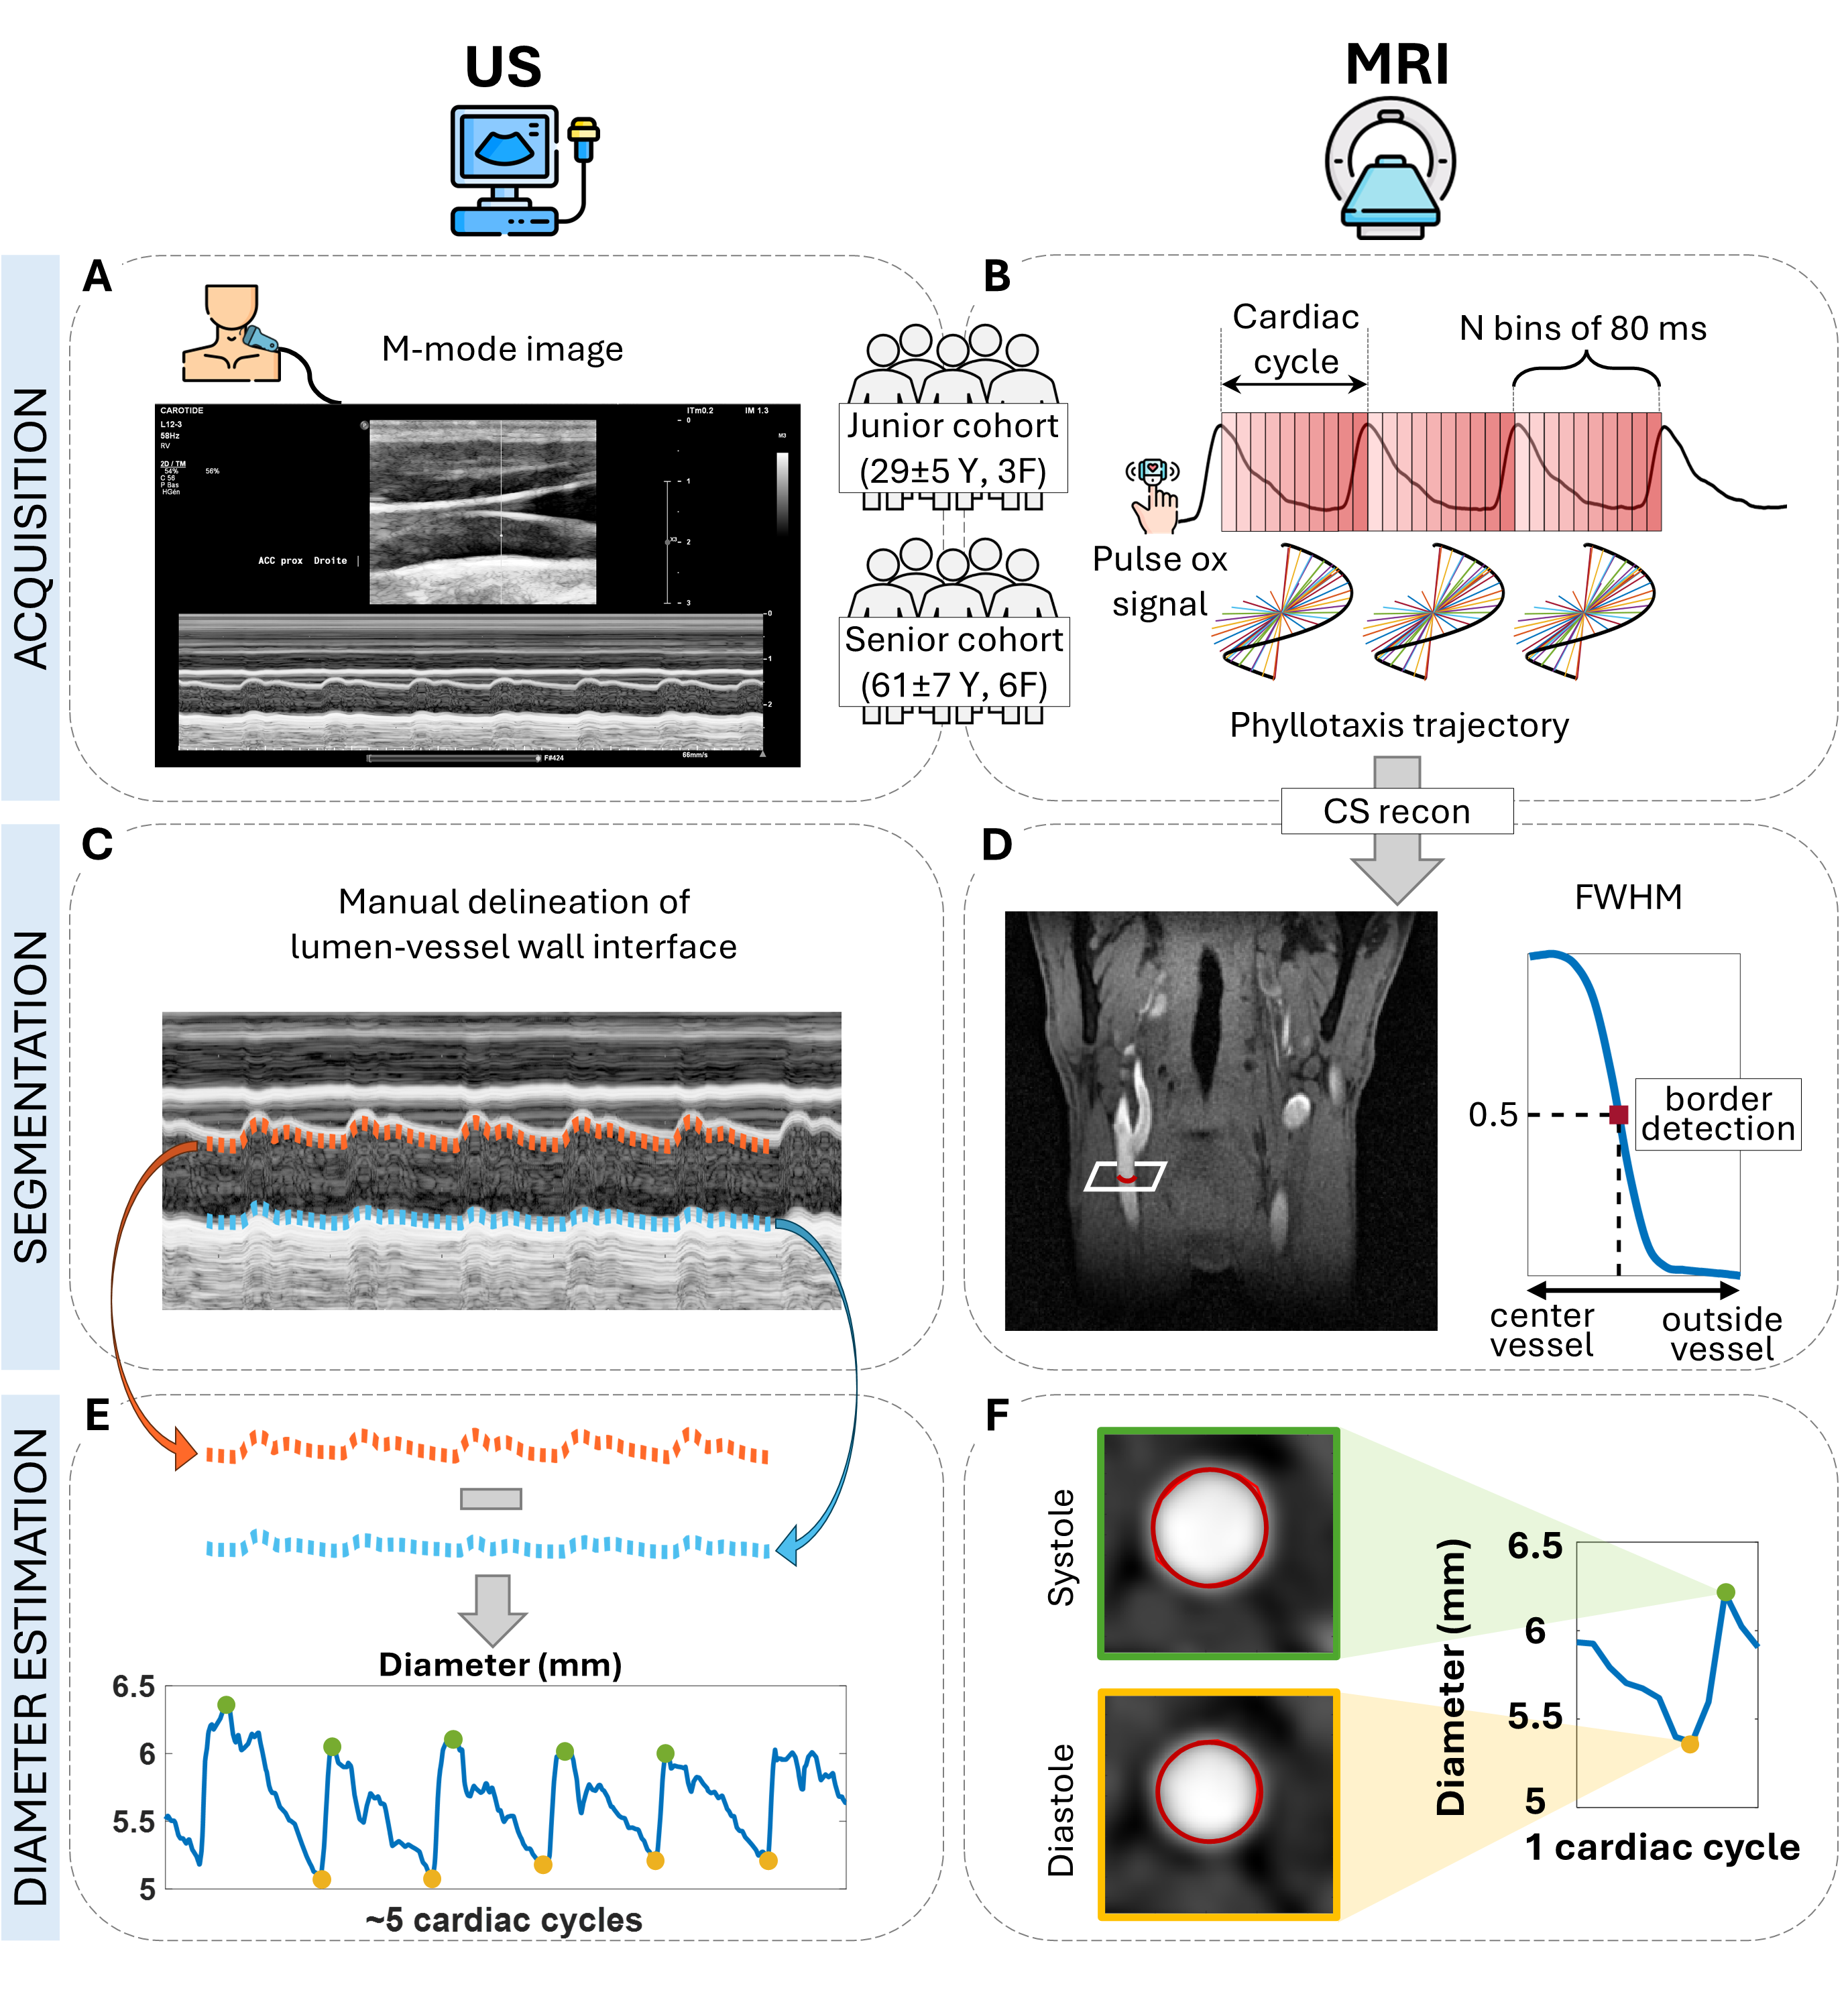

Results: As expected, the CCA β measured with MRA (βjunior_MRA=3.8±0.9 vs βsenior_MRA=5.4±1.0, p=0.002) and US (βjunior_ US=3.5±0.7 vs βsenior_ US=7.2±3.0, p=0.005) was significantly higher in the senior cohort (Fig. 2A). When comparing modalities, there was no significant US-MRA difference in the junior (p=0.5) or senior (p=0.08) cohorts. The PWV was significantly higher for the senior cohort with both MRA (PWVjunior_MRA=5.2±0.7m/s vs PWVsenior_MRA=6.5±0.9m/s, p=0.0005) and US (PWVjunior_US=5.0±0.5m/s vs PWVsenior_US=7.4±1.7 m/s, p=0.003, Fig. 2B). No significant PWV differences were observed between the two modalities. MRA presented excellent repeatability with higher ICC than US (ICCMRA=0.94 vs. ICCUS=0.67) and lower CV (CVMRA=1.7% vs. CVUS=3.8%).

Figure 2. Three example orthogonal anatomical views of the neck and carotid arteries in the MRA in a junior participant together with a 3D rendering of the carotid arteries. While the arterial blood has a bright signal, the lipid signals are largely suppressed by the water excitation. Figure 3. Stiffness-related measurements for both modalities and cohorts in the common carotid arteries. (A) Stiffness index (β) measurements showed no statistical significance between modalities while there was an age-related increase of β when comparing the junior and senior cohorts (p_MRA = 0.002 and p_US = 0.005).(B) Local pulse wave velocity (PWV) values were significantly higher for the senior cohort in both modalities (p_MRA = 0.0005 and p_US = 0.003) while there were no statistical differences between MRA and US.

Figure 3. Stiffness-related measurements for both modalities and cohorts in the common carotid arteries. (A) Stiffness index (β) measurements showed no statistical significance between modalities while there was an age-related increase of β when comparing the junior and senior cohorts (p_MRA = 0.002 and p_US = 0.005).(B) Local pulse wave velocity (PWV) values were significantly higher for the senior cohort in both modalities (p_MRA = 0.0005 and p_US = 0.003) while there were no statistical differences between MRA and US.